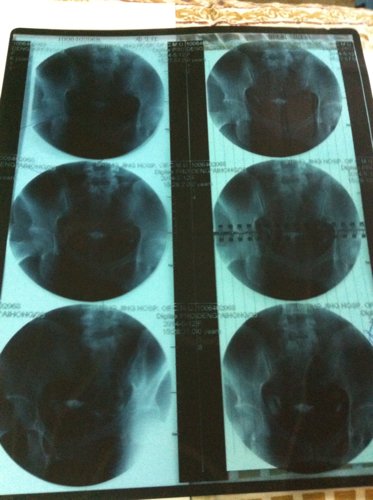

请问我左边输卵管僵硬,右边积水该怎么治?除了手术能有别的办法吗?能怀孕吗?医生建议做试管,也要治好积水才能做。还有更好的办法吗?请高手指点,详细些。谢谢了!在线等,急!!!

病情分析: 你的去看必要时选择腹腔镜手术观察是否改善的情况,注意休息的 指导意见: 平时的情况调整饮食和情绪,但是考虑输卵管双侧都不好的情况影响正常怀孕的,必要时选择试管较好的,加强营养的